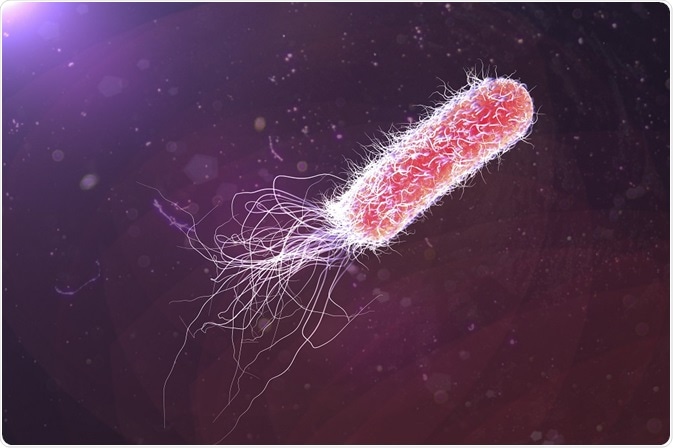

Pseudomonas aeruginosa is a human pathogen which can cause life-threatening illness, especially in people who have a depleted immune system. One of the ways P. aeruginosa causes infection is through quorum sensing; a type of cell signalling pathway that initiates the production of virulence factors.

P. aeruginosa is a gram-negative bacterium whose virulence depends on a large number of extra- and intracellular factors. Infections typically affect those in hospital (hospital-acquired infections), where there are strong selective pressures for more hardy, dangerous bacteria.